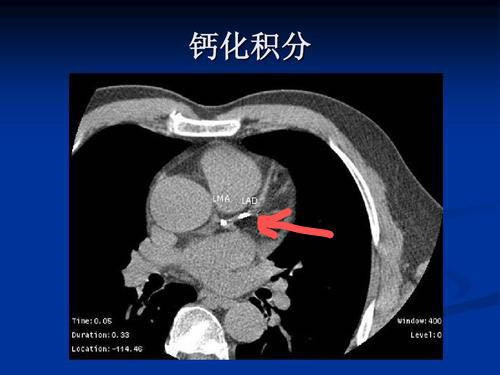

结果看什么?看那些威胁健康的“白色阴影”(图中标示箭头部位均为钙化部位)

CT:钙化会在CT影像中呈现为白色的高密度影,下图所示为冠脉壁钙化部位。